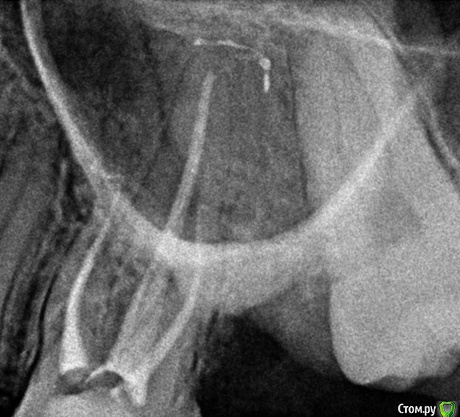

Снимок сделан спустя месяц после пломбировки к/к:

post-50922-0-77771600-1517779998_thumb.jpg